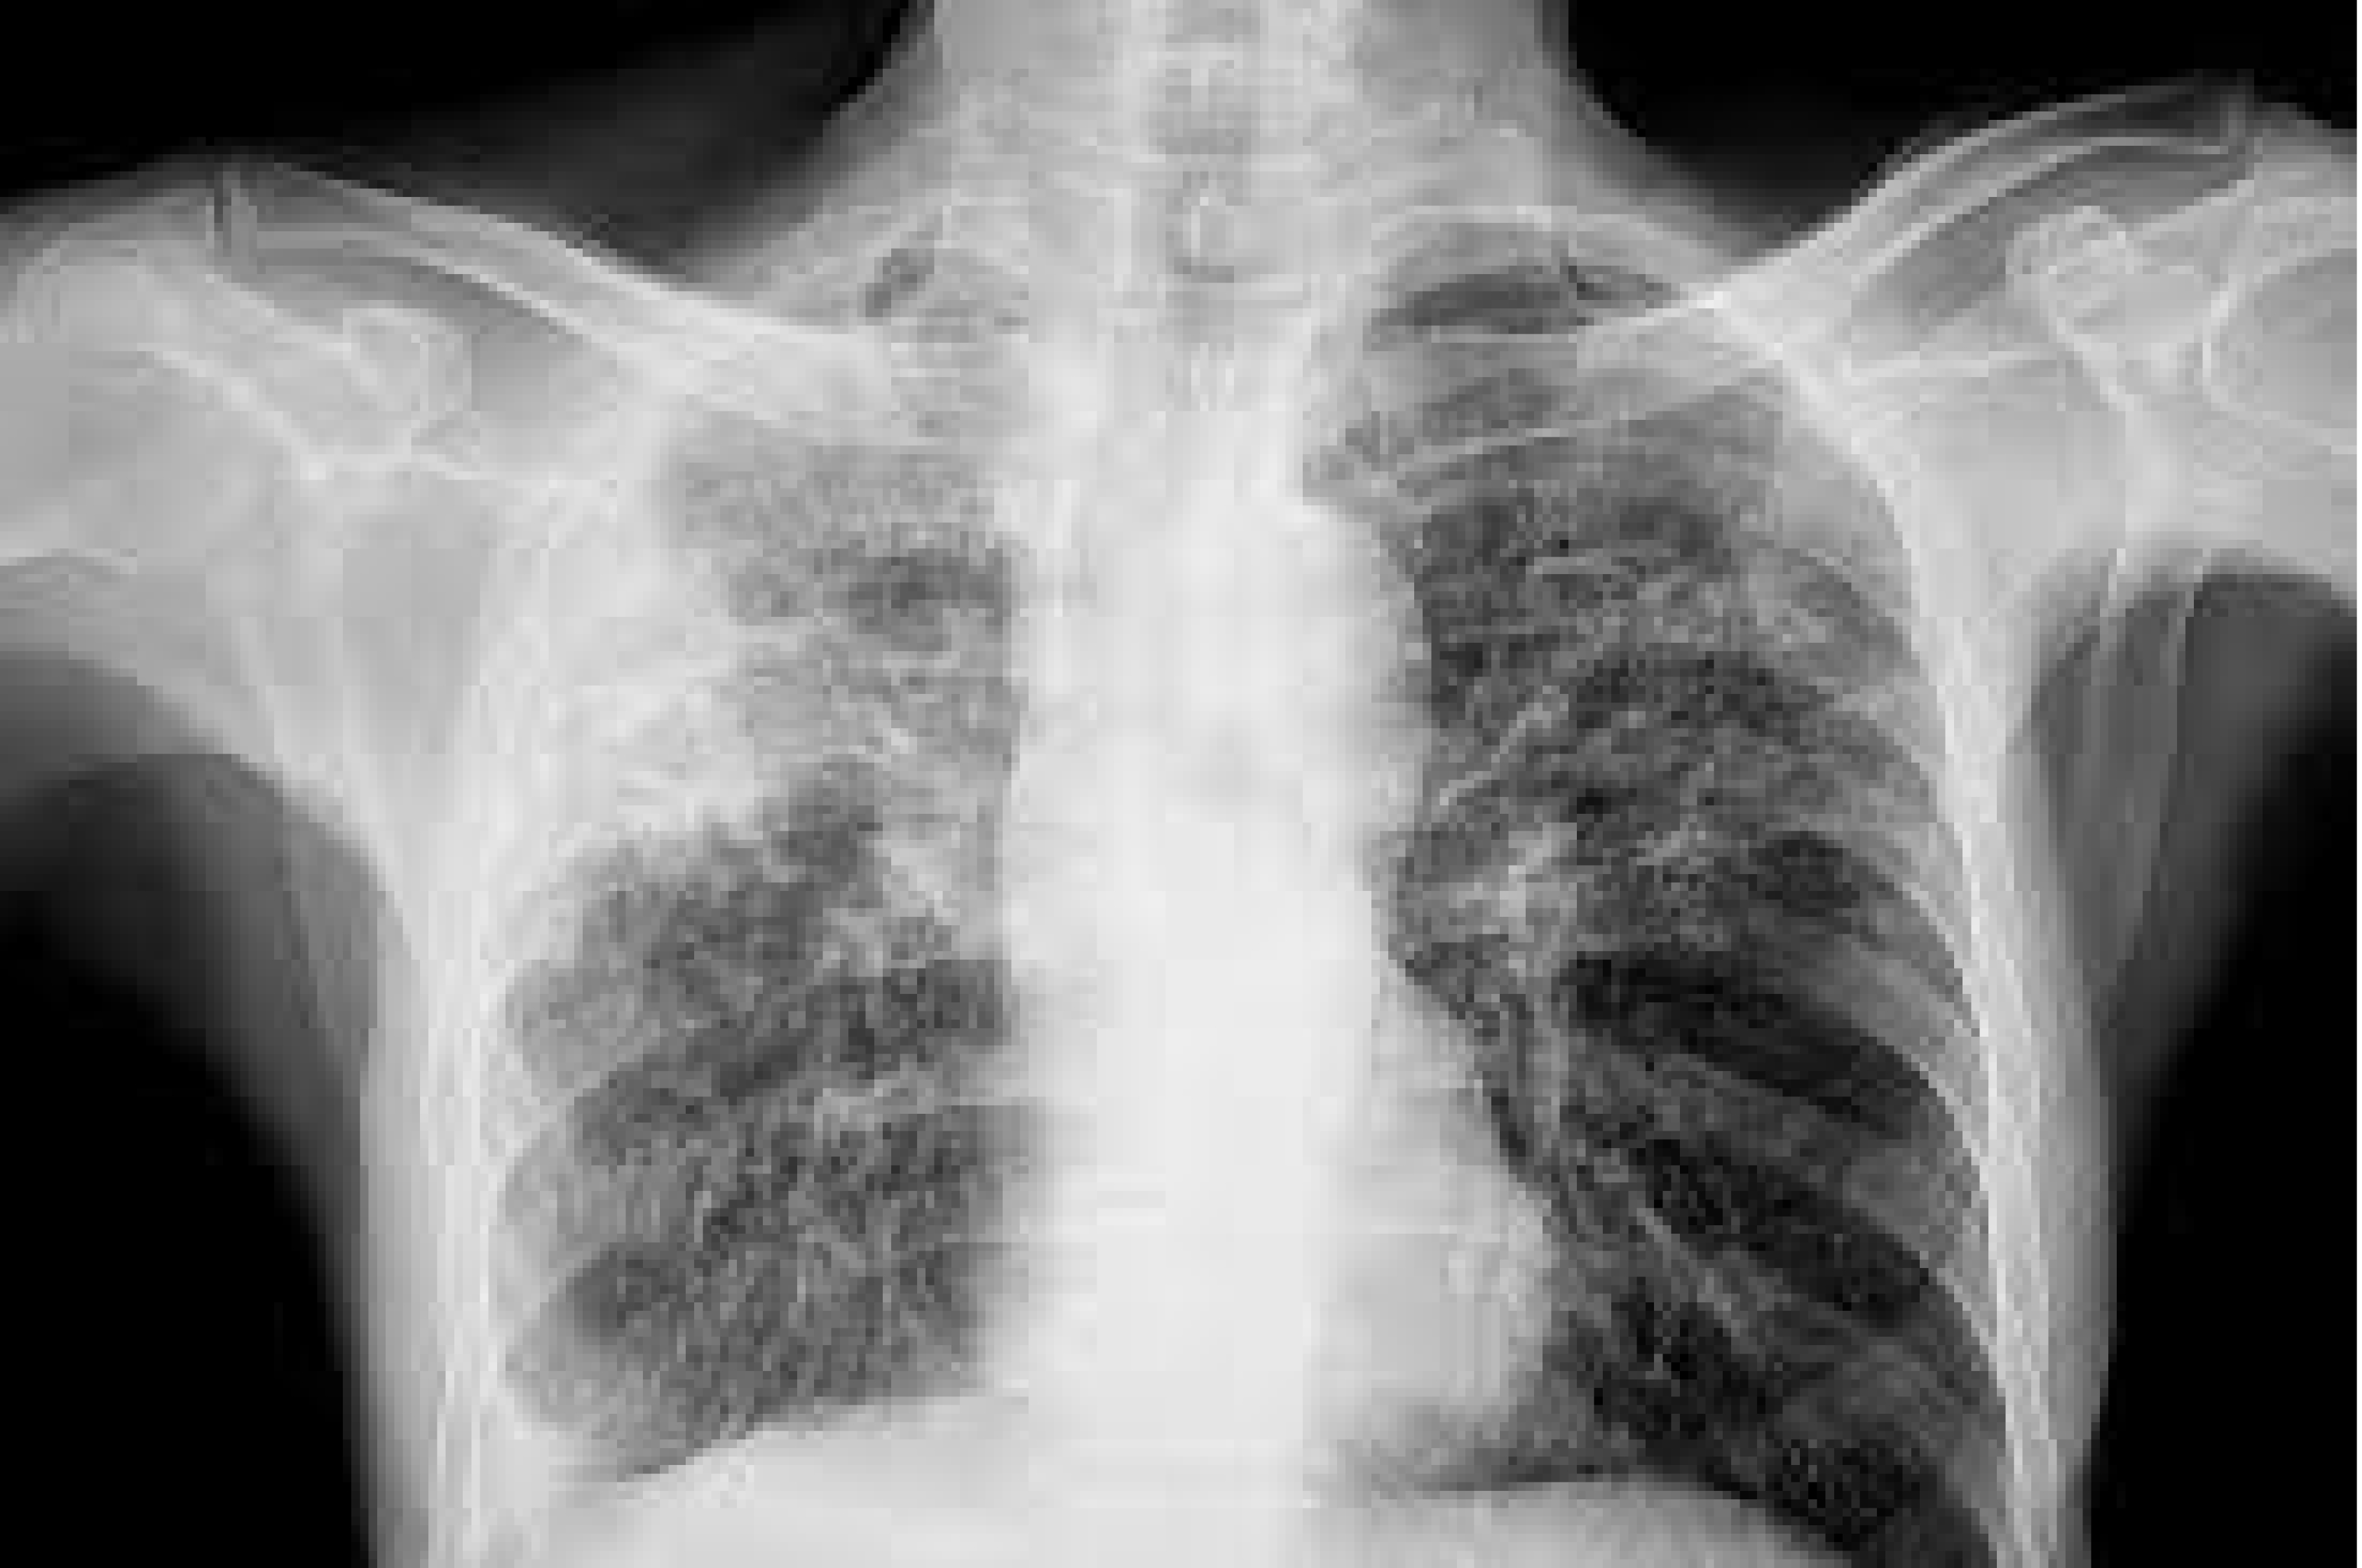

La tuberculose reste l’une des maladies infectieuses qui entraînent le plus de décès dans le monde. Chaque jour, plus de 3300 personnes perdent la vie des suites de la tuberculose et plus de 29 000 autres contractent cette maladie pourtant évitable et curable. On estime que les efforts déployés à l’échelle mondiale pour lutter contre la tuberculose ont permis de sauver 83 millions de vies depuis 2000, cependant les coupes budgétaires subies par l’action sanitaire mondiale menacent de réduire ces progrès à néant. L’adoption d’outils de diagnostic rapide pose des difficultés dans de nombreux pays, en partie en raison de leur coût élevé et de la nécessité d’acheminer les échantillons à l’appui des analyses vers les laboratoires centralisés.